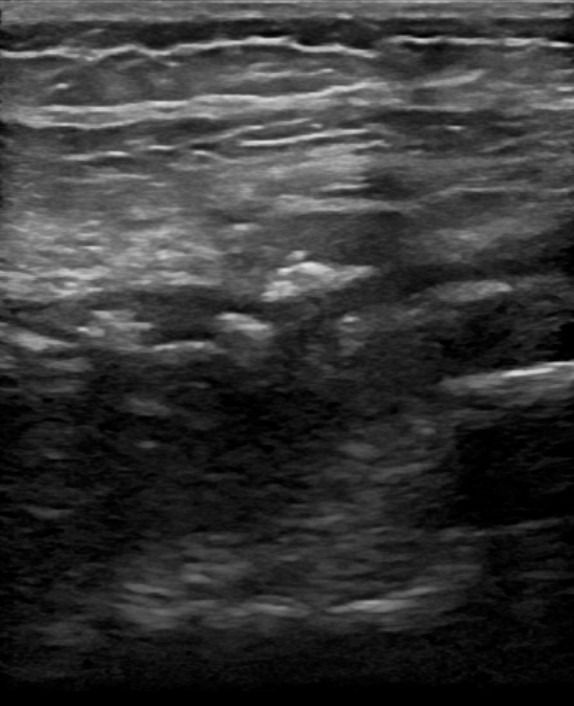

- Τενοντοπάθεια ή ρήξη γλουτιαίων τενόντων, ορθού μηριαίου και οπίσθιου μηριαίου

- Τροχαντηρίτιδα: συλλογή υγρού στους θυλάκους των γλουτιαίων τενόντων στο μείζονα τροχαντήρα

- Θυλακίτιδα: Συλλογή υγρού στο θύλακο του τένοντα του Λαγονοψοΐτη